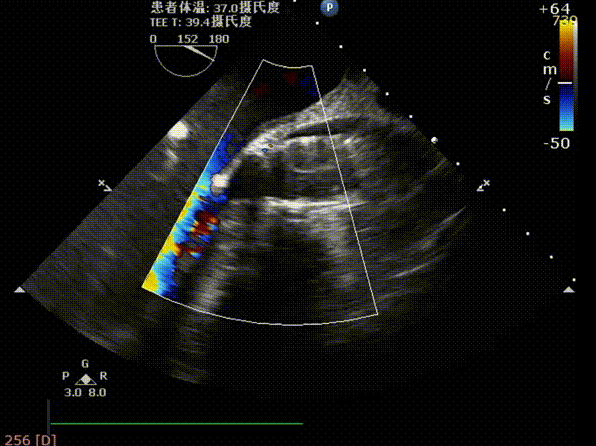

术前TEE评估主动脉瓣

释放后超声评估

释放后超声下多切面评估,瓣膜位置可,无明显瓣周漏

测得主动脉瓣流速由5.4m/s改善至1.9m/s